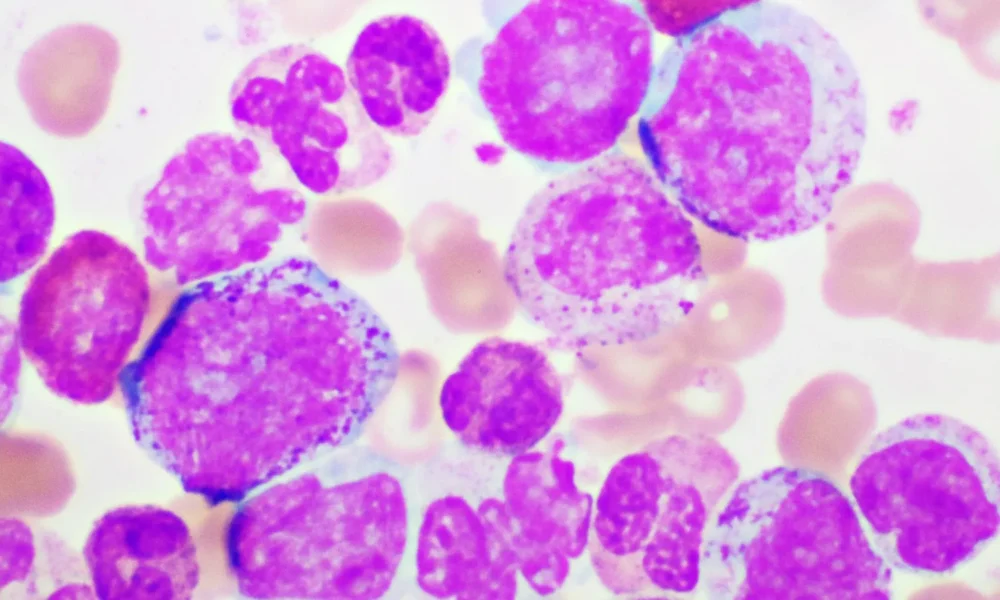

BioPharma Dive – AI / Data3 months agoMerck to buy Terns in $6.7B bet on a ‘differentiated’ leukemia drug

If consummated, the deal would hand Merck a treatment that could challenge Novartis’ fast-selling Scemblix. But the low purchase premium — which one analyst described as...